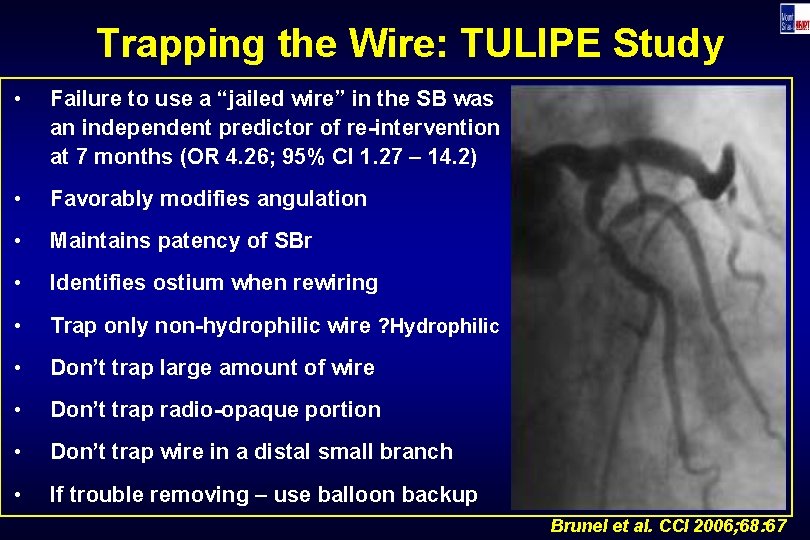

Trapping the Wire: TULIPE Study • Failure to use a “jailed wire” in the SB was an independent predictor of re-intervention at 7 months (OR 4. 26; 95% CI 1. 27 – 14. 2) • Favorably modifies angulation • Maintains patency of SBr • Identifies ostium when rewiring • Trap only non-hydrophilic wire ? Hydrophilic • Don’t trap large amount of wire • Don’t trap radio-opaque portion • Don’t trap wire in a distal small branch • If trouble removing – use balloon backup Brunel et al. CCI 2006; 68: 67